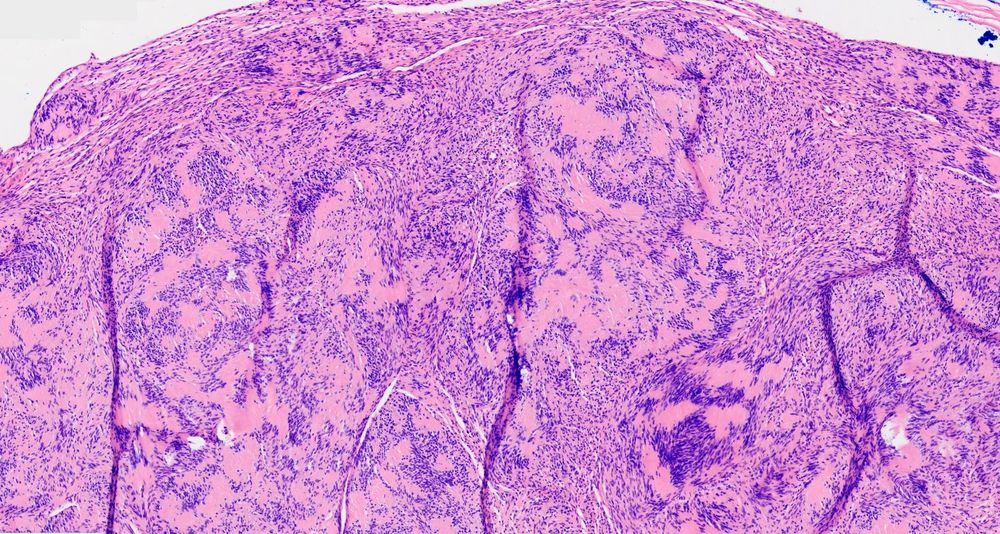

Image of the Week!

Submitted by: Miruna C. Popescu, M.D.

Directory Profile: buff.ly/dc1Jnsa

Subspecialty: Bone, joints & soft tissue

Diagnosis: Plexiform neurofibroma

#Pathology #PathologyOutlines #BSTPath #PathSky